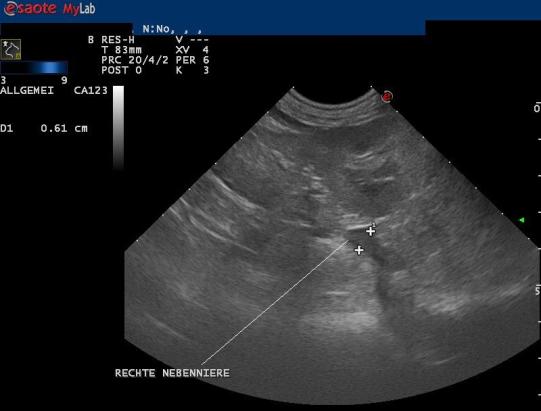

Zur Diagnosesicherung wird ein sogenannter ACTH-Stimulationstest durchgeführt. Hierbei wird der Cortisolwert im Blut vor und nach einer Injektion mit einem Hormon (ACTH), welches die Nebennieren zur Cortisolproduktion anregt, gemessen. Bei Luca steigt der Cortisolwert nach der Injektion extrem an und bestätigt dadurch den Verdacht einer Nebennieren-Überfunktion. Ein weiterer Bluttest sowie ein Ultraschalluntersuch, bei welchem eine vergrösserte linke Nebennieren gefunden wird, komplettieren die Diagnose eines adrenalen (nebennierenbedingten) Cushing-Syndromes.

Zu einer Nebennierenüberfunktion kann es einerseits kommen, wenn sich in einer Nebenniere ein hormonproduzierender Tumor entwickelt (adrenaler Cushing's, ca 15% der Fälle). Typisch ist bei diesen Hunden, dass eine Nebenniere deutlich vergrössert und die andere Nebenniere eher klein ist. Etwa die Hälfte dieser Nebennierentumoren bilden Ableger (Metastasen). In ca 85% der Hunde mit Nebennierenüberfunktion entwickelt sich ein Tumor in der Hirnanhangsdrüse, welcher eine Vergrösserung beider Nebennieren gleichzeitig bewirkt (hypophysärer Cushing's). Zur Differenzierung der beiden Formen kann neben einer Blutuntersuchung auch ein Bauchultraschall oder idealerweise eine Hirnuntersuchung mittels Computertomographie oder Magnetresonanztomographie durchgeführt werden.